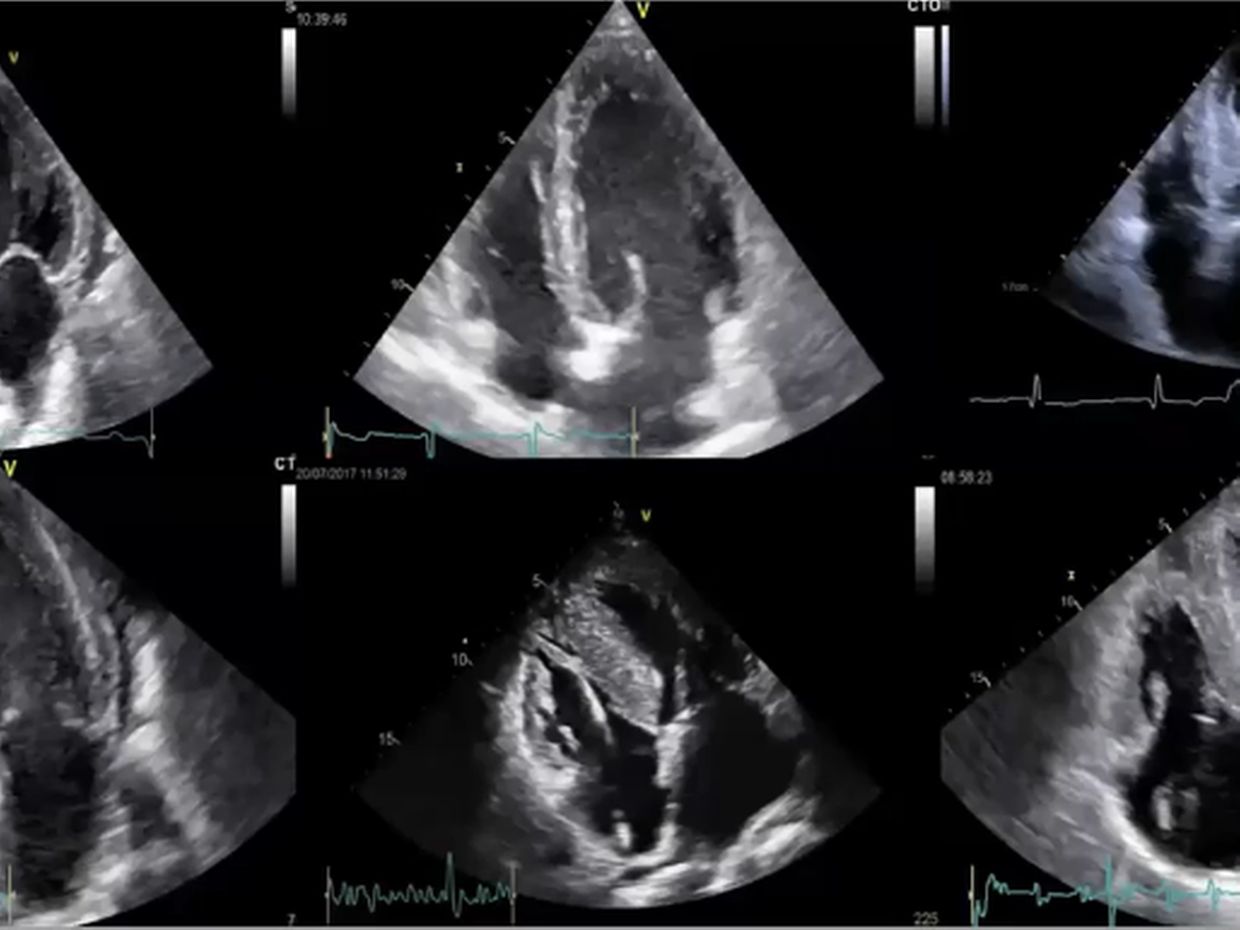

Der Stellenwert der Echokardiografie als Screening-Tool und zur Verlaufskontrolle bei hypertrophen Kardiomyopathien steht im Fokus dieses Videolearnings. Sie erfahren, warum mit der Echokardiografie keine endgültige Diagnose möglich ist, diese aber gegebenenfalls die weitere Abklärung anstößt.